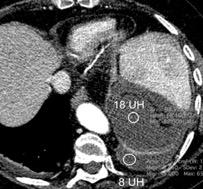

Hemorrágica………….30-70 UH

Extravasación iv. con sangrado activo……….>90 UH

“Simpático”………….,,,,<15 UH

Durso AM et al. Penetrating Thoracic Injury. Radiol Clin N Am 2015.

Urogénico……………….< 15 UH

Entérico.. ………………+/- 15UH

Biliar, Quiloso……………..<0 UH

68 UH

12UH

Abramowitz1 Y et al. Pleural Effusion: Characterization with CT Attenuation Values and CT Appearance .AJR 2008